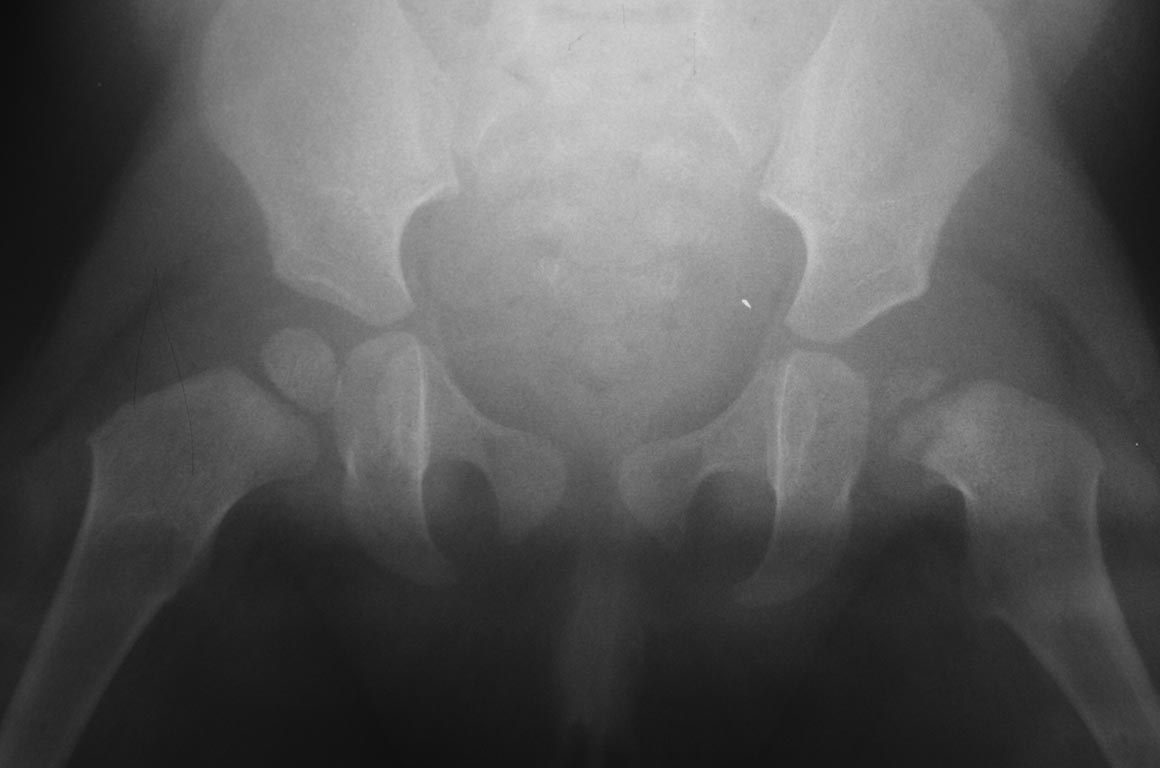

Добрый вечер уважаемые коллеги. Помогите советом, в какую клинику и к кому обратится с данной проблемой (у ребенка в возрасте 1мес. диагностирован гематогенный остеомиелит головки бедра).

Лечили консервативно (выписку и фото в динамике прилагаю). На сегодняшний день ребенку 11 мес. Детские ортопеды по месту сомневаются в тактике( в плане операции или выжидательная тактика). Хотелось проконсультироваться с теми кто занимается этой проблемой.Заранее спасибо. С ув. Андрей

По факту снимков-справа т/б сустав(снимок №6) также не в порядке - в состоянии подвывиха-головка почти на треть вне впадины, снимок №7 - непонятная укладка